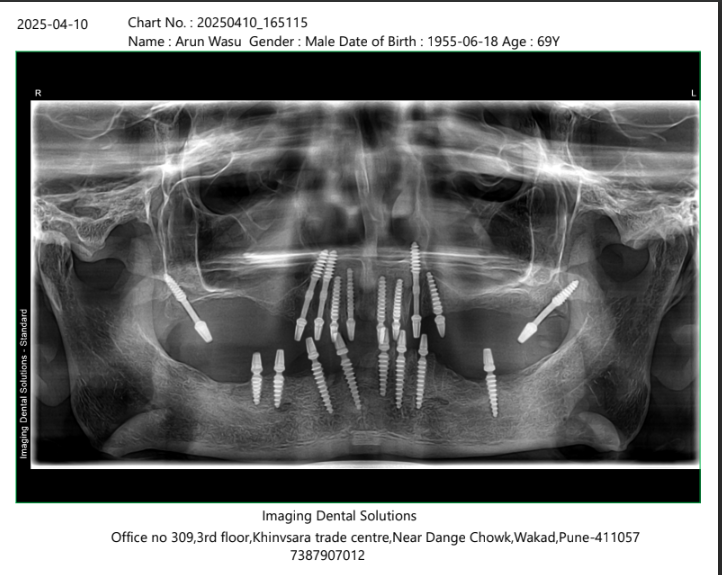

X-Ray Analysis

OPG — After

Radiographic Findings

The OPG shows multiple dental implants placed in both upper and lower jaws. The implants are distributed across the jaw to provide strong support for full arch fixed teeth. Angled implants are used in certain areas to maximize bone utilization and avoid critical anatomical structures. This confirms a successful full mouth rehabilitation, allowing immediate loading and stable fixed teeth even in an elderly patient.